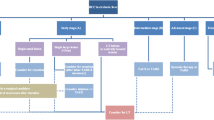

Current LI-RADS Imaging Criteria for HCC Diagnosis

The LI-RADS CT/MRI diagnostic algorithm can only be applied to a specific target population in which the pretest probability of HCC is sufficiently high to attain high specificity (> 95%) of LR-5 (definite HCC) criteria [10]. Each liver observation is categorized from LR-1 (definitely benign) to LR-5, with the categories from 1 to 5 reflecting increasing likelihood of HCC [11••]. LR-1 and LR-2 observations are categorized as definitive or probably benign, respectively [5••]. LR-3 to LR-5 categories correspond to intermediate probability of malignancy, probable HCC, and definite HCC, respectively. The LR-5 category is intended to be 100% specific for HCC, which would preclude the need for percutaneous biopsy for definitive diagnosis [12]. In addition to LR-1 through LR-5, an LR-M (probably or definitely malignant, not HCC specific) category can be assigned to observations that are probably or definitely malignant, but the imaging features are not specific for HCC [13]. While approximately 36% of LR-M observations are HCC, a majority of LR-M represent other malignancies, such as intrahepatic cholangiocarcinoma (iCCA), which may arise in the same at-risk population [14]. The final category, LR-TIV (definite tumor in vein) is used for malignancy that has definite macrovascular invasion on imaging [15]. The assignment of LR-3 to LR-5 categories is based on the combination of major imaging features (i.e., “nonrim arterial phase hyperenhancement [APHE], nonperipheral washout appearance [WO], enhancing capsule appearance, size, and threshold growth [16]) as well as ancillary imaging features, from which a category can be determined by using the CT/MRI diagnostic table [9].

LI-RADS treatment response algorithm was released in 2017, to provide a step by step approach for assessment of lesions following LRT [5••, 59]. LI-RADS TRA, modeled after mRECIST, not only includes APHE as a criterion to detect viable tumor but also incorporates imaging findings of washout appearance or treatment-specific enhancement pattern [5••]. Another distinguishing characteristic of LI-RADS TRA is that it provides assessment at a lesion level, which is important for clinical management, as individual lesions may be treated by different LRT over time, with distinct responses.

The LI-RADS treatment response categories include LR-TR nonviable, LR-TR equivocal, LR-TR viable, and LR-TR nonevaluable. A unique aspect of LI-RADS TRA is the inclusion of the category of LR-TR equivocal, which allows reporting of lesions in which the imaging appearance does not meet criteria for viable or nonviable disease. Treated tumors are characterized as equivocal when enhancement is atypical for treatment-specific enhancement pattern and not meeting criteria for probably or definitely viable tumor. In this scenario, short-term follow-up imaging is recommended, as opposed to immediate retreatment [1, 5••, 12, 13]. The LR-TR equivocal category is particularly important for tumors treated with intra-arterial and radiation-based therapies which target not only the tumor itself but also the hepatic parenchyma adjacent to the treated tumor, resulting in perfusional alterations visible on post-treatment imaging. In such instances, use of the LR-TR equivocal category helps to prevent unnecessary retreatment. While there is a risk that viable tumor is left untreated, HCC is generally a slow-growing tumor with a doubling time of 86–117 days [60,61,62], thus a wait and watch approach with a 3-month interval imaging may be a safe approach to differentiate residual viable disease from benign parenchymal perfusional alterations.